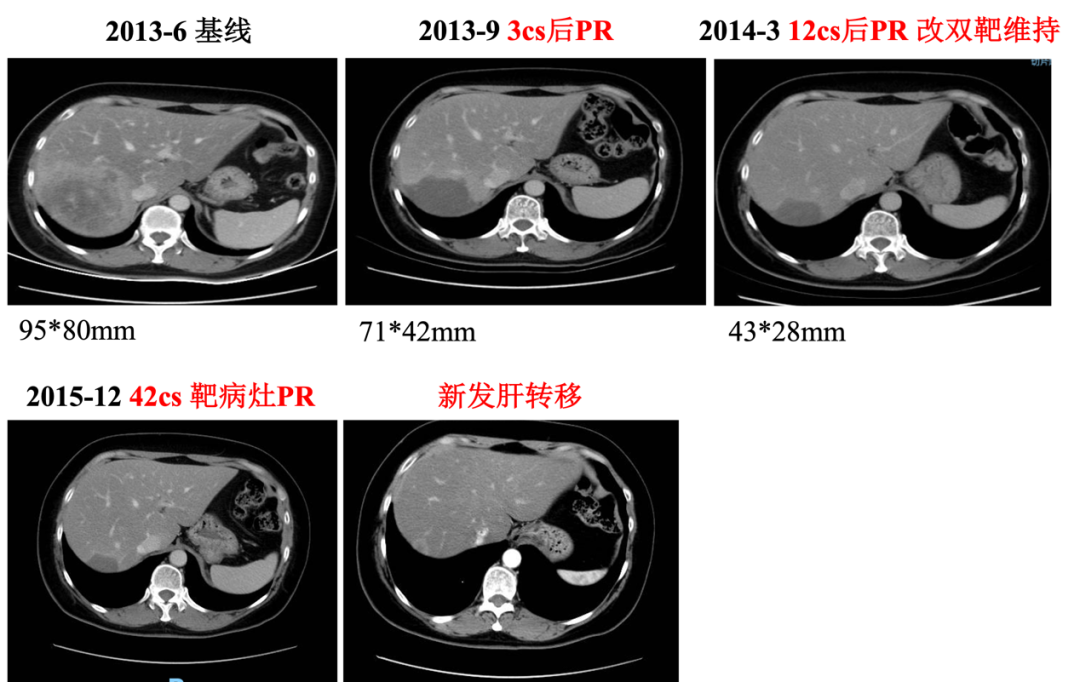

▌影像学检查:

2013年6月30日腹部CT:肝右后叶病灶并肝内多发子灶,考虑M,病灶总范围8.0*5.8cm,其病灶周围可见多发异常廓清子灶(4-5个),最大约1.6cm;

图1. 腹部CT

▌诊断:

右乳浸润性导管癌改良根治术后复发 pT2N0M0 ⅡA期→Ⅳ期

HER2扩增型(非Luminal型)

肝转移

骨转移